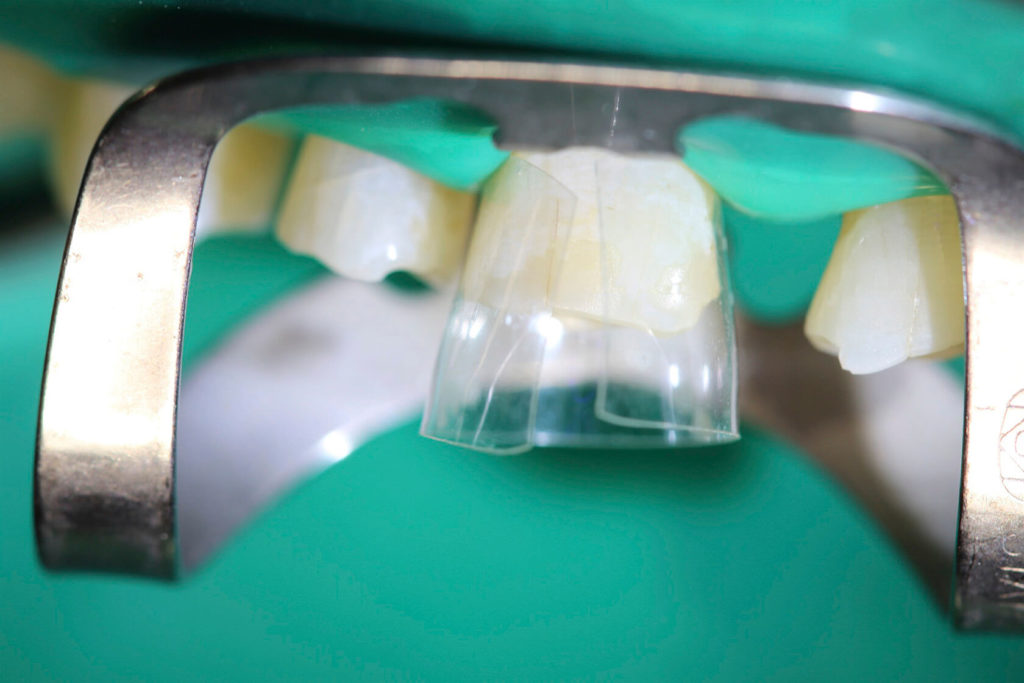

This 50 year old patient was in today for a check-up on his teeth. I had not seen him for 20 months since we restored his lower teeth. We had restored his upper teeth 2 months previous to doing his lower teeth. He came from another neighboring dental office where they don’t do composite rehabs. He has been into this other office for several cleanings since we did his rehab but he smokes, loves his coffee and has lots of stain. Anyway I was wondering how he was making out with his new teeth and he was very satisfied. In his words “no pain or sensitivity or problems”. So I was quite happy with his rehab. His wife came as well and we knew each other from 30 years ago when my daughters and I were riding horses in the same horse club. There were a few air bubbles that I didn’t like and a small open margin that I repaired and that was all he needed to spiffy him up.